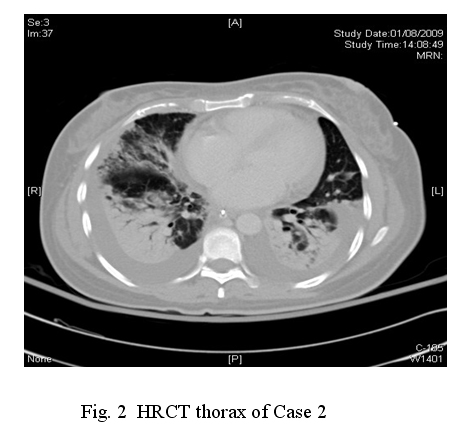

During her ICU stay, she required a long period of high PEEP of up to 28cmH2O for around 12 days while she was on mechanical ventilation. She had MRSA and Acinetobacter infections, with Vancomycin and Ciprofloxacin being prescribed. There was also the development of acute coronary syndrome, as evidenced by new T wave inversion over anterior leads and raised troponin I. Echocardiogram showed impaired left ventricular contraction with an ejection fraction (EF) of 40% only, together with hypokinesia over anteroseptal and apical segments of left ventricle. Aspirin was started. Improvement of left ventricular function (EF 71%) was observed in the follow-up echocardiogram on 24/8/09. Enoxaparin had been given for 10 days for prophylaxis of thromboembolism. Fortunately, her condition improved and she was able to come off ventilator support. The total duration of mechanical ventilation and ICU stay were 23 and 33 days respectively. She received further rehabilitation in general ward with much improvement. On Day 45 of admission, she was discharged home. She was able to walk unaided with no shortness of breath. CXR before discharge showed residual fibrosis mainly over both lower zone and HRCT thorax on Day 49 showed ground glass attenuation, streaky shadows and small cystic areas in both lung fields compatible with residual fibrosis & bronchiectasis due to previous inflammation. (Fig.2)

Lung function test on Day 52 showed evidence of restrictive lung disease, with the post bronchodilator FEV1 being 1.95L (82% predicted) and FVC 2.0L (71% predicted). The ratio of FEV1/FVC was 97.3%. Her vital capacity(VC) read 1.95L (69% predicted) while the residual volume (RV) and total lung capacity registered 0.96L (60% predicted) and 2.91L (59% predicted) respectively.